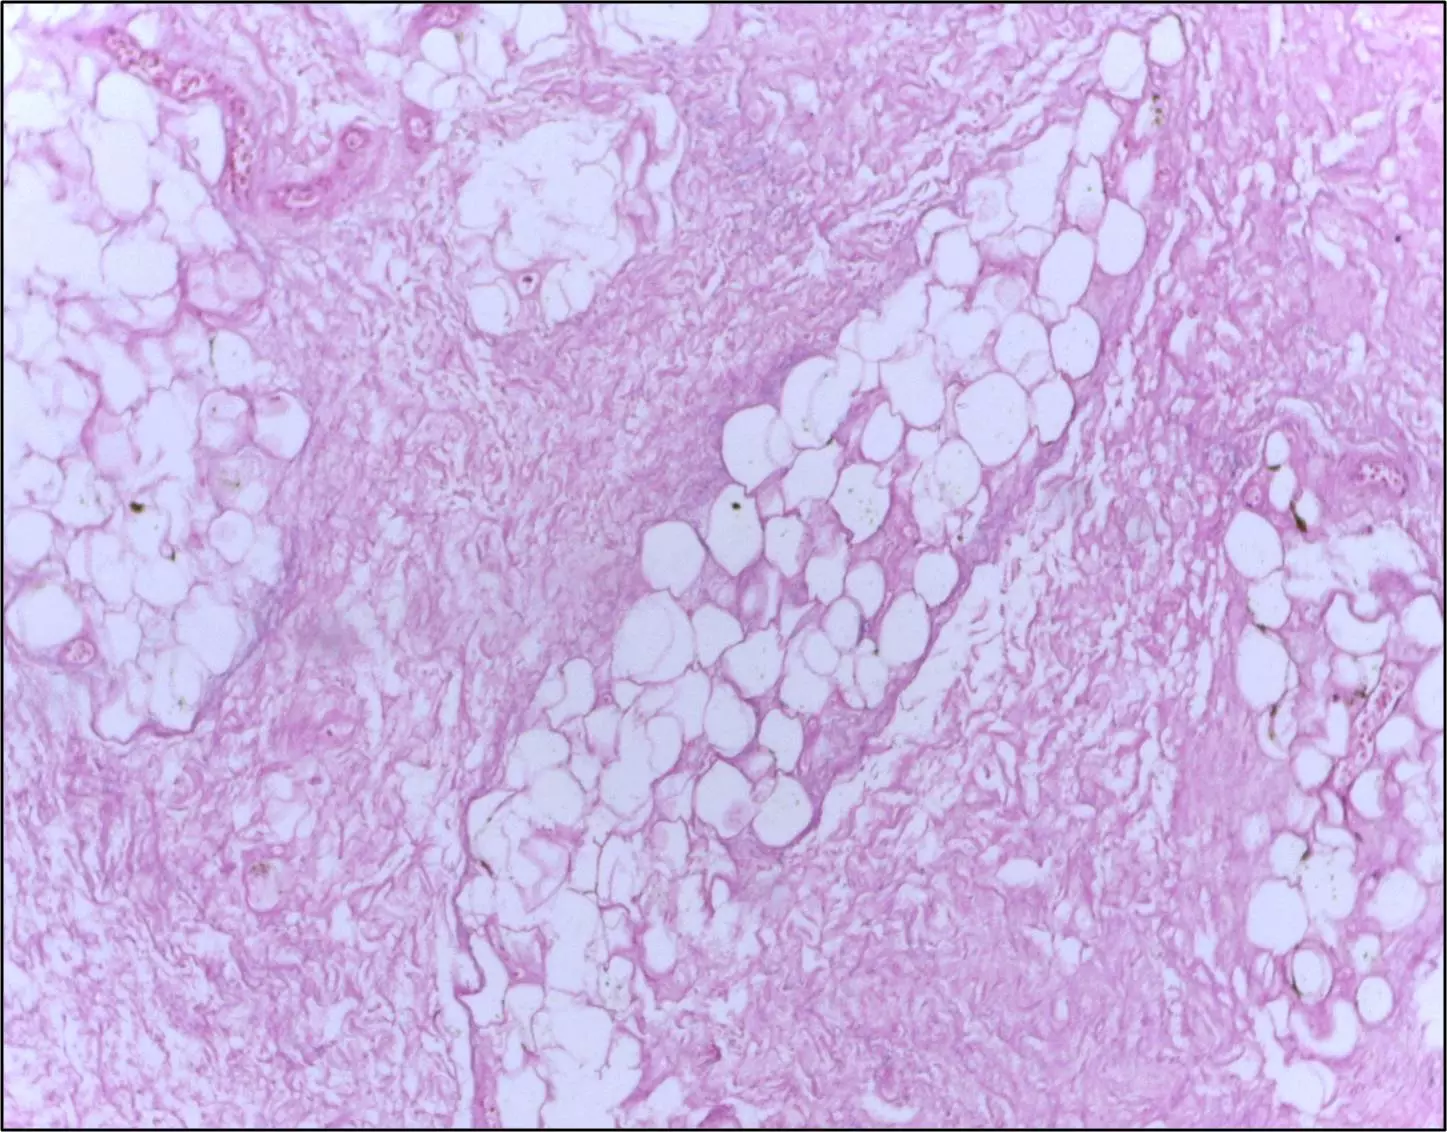

Fat necrosis presents as irregular, firm, palpable masses with or without skin changes meaning it mimics breast cancer clinically, and so should be referred for further imaging. The necrosis is the result of an inflammatory response either post trauma or surgery of the breast, and so this should always be asked about in the history.

Image - Histological breast tissue showing fat necrosis. There are necrotic adipocytes surrounded by an inflammatory response with cholesterol clefts

Creative commons source by Department of Pathology, Calicut Medical College [CC BY-SA 4.0 (https://creativecommons.org/licenses/by-sa/4.0)]